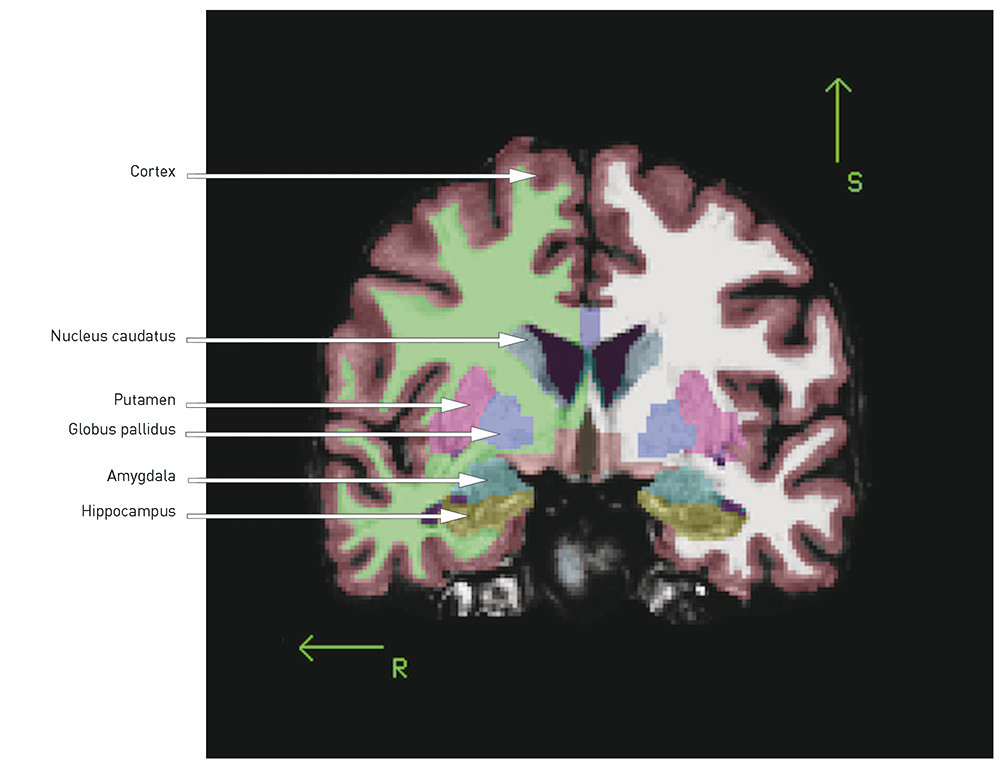

When the total volume is smaller and the ventricles enlarged, the question is whether there are certain regions or structures where the volume reduction is more pronounced. The following is a brief review of the best replicated findings (for illustration, see Figs. 1 and 2):

Fig. 1  Coronal section of T1-weighted MR image, automatic volume estimation using MRI post-processing tool FreeSurfer. R =…

Fig. 1 Coronal section of T1-weighted MR image, automatic volume estimation using MRI post-processing tool FreeSurfer. R = right, S = superior